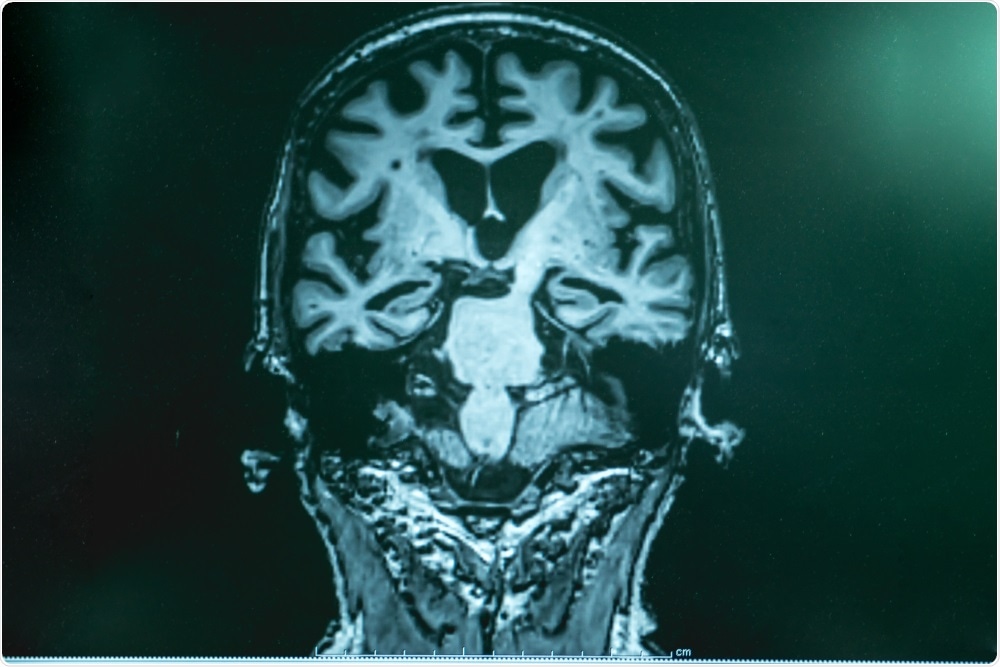

Image Credit: Gorodenkoff/Shutterstock.com

Furthermore, within the last couple of decades, advances in computer technology have led to the emergence of computational neuroscience, and advances in imaging techniques have greatly improved diagnostic and research imaging tools to study brain structure and function.

Cognitive and behavioral neuroscience focuses on how psychological functions are produced in the brain or related to neural activity. This can be studied using animal models or human subjects by an array of imaging techniques such as fMRI, PET & EEG, correlating brain signals (BOLD or electrical) to specific tasks or functions in the field of neuropsychology.